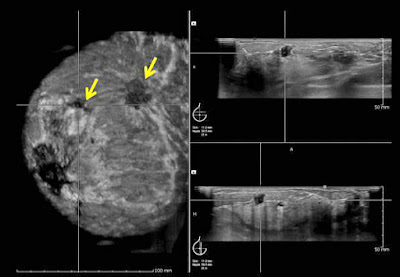

ΥΠΕΡΗΧΟΓΡΑΦΙΚΑ ΕΥΡΗΜΑΤΑ

Κακοήθους βλάβης

Είναι ακιδωτού σχήματος ή μικρολοβώδης σε ίση, περίπου, συχνότητα ενώ, με χαμηλότερη συχνότητα, παρουσιάζεται ανωμάλου σχήματος ή με βάθος μεγαλύτερο του πλάτους. Είναι σαφώς συχνότερα υποηχογενής και, μερικές φορές, συνοδεύεται από επασβεστώσεις ή πορεκτασία. (Διάταση των μαστικών πόρων).

• Το υπερηχογράφημα μαστών χρησιμοποιείται επίσης στην σταδιοποίηση των ασθενών με καρκίνο του μαστού, επιτρέποντάς μας να μετρήσομε με ακρίβεια το μέγεθος του όγκου και να εντοπίζομε επιπρόσθετες εστίες σε περιπτώσεις πολυεστιακής εντόπισης της βλάβης.

Διαδοχικές μετρήσεις του όγκου πρίν και μετά από τη χημειοθεραπεία μπορούν να χρησιμοποιηθούν για να εκτιμήσομε αντικειμενικά την απάντηση του ασθενή στο σχήμα της χημειοθεραπείας.